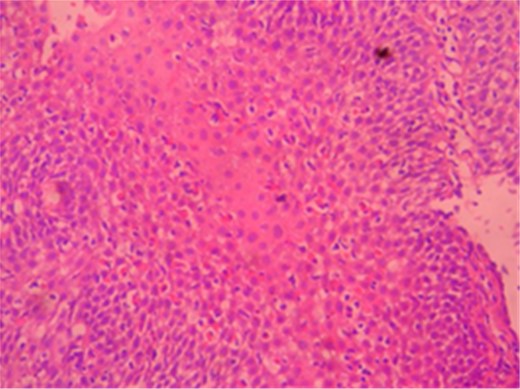

A male patient of 35 years age presented to our General Surgery Clinic with complaints of difficulty in swallowing, sensation of food sticking in the back of the breast while eating, stomach ache, weight loss and weakness for nearly a year. The fact that the symptoms chiefly arose upon ingestion of dairy products was interesting. Normal values were obtained for complete blood count serum CRP, sedimentation and total serum IgE of the patient. Standing abdominal X-ray and abdominal ultrasonography failed to reveal any evidence of pathology. Mucosal fissure and erosional areas were observed in the middle distal esophagus using upper GI endoscopy and are probably associated with reflux esophagitis; biopsies were made of the same (Fig. 1). Bulbitis and pangastritis were observed in the duodenum and stomach and biopsies were made. Pathological examinations of the endoscopic biopsies revealed evidence of chronic esophagitis in esophagus, chronic Helicobacter pylori-positive pangastritis in stomach and chronic duodenitis in the duodenum. The examination showed eosinophilic infiltration only in the esophagus (Fig. 2). Histological examination (40 X) revealed more than 30 eosinophils per field (Fig. 3). The patient was diagnosed with eosinophilic esophagitis and administered dexamethasone I.M as well as treatment for H. pylori eradication which resulted in relief of the symptoms. The patient was also instructed to avoid consumption of milk and dairy products, which caused the development of symptoms. The control endoscopic examination and pathological evaluation made after 3 months, failed to reveal evidence of esophageal eosinophilic infiltration, relapse did not occur during the following 2 years.